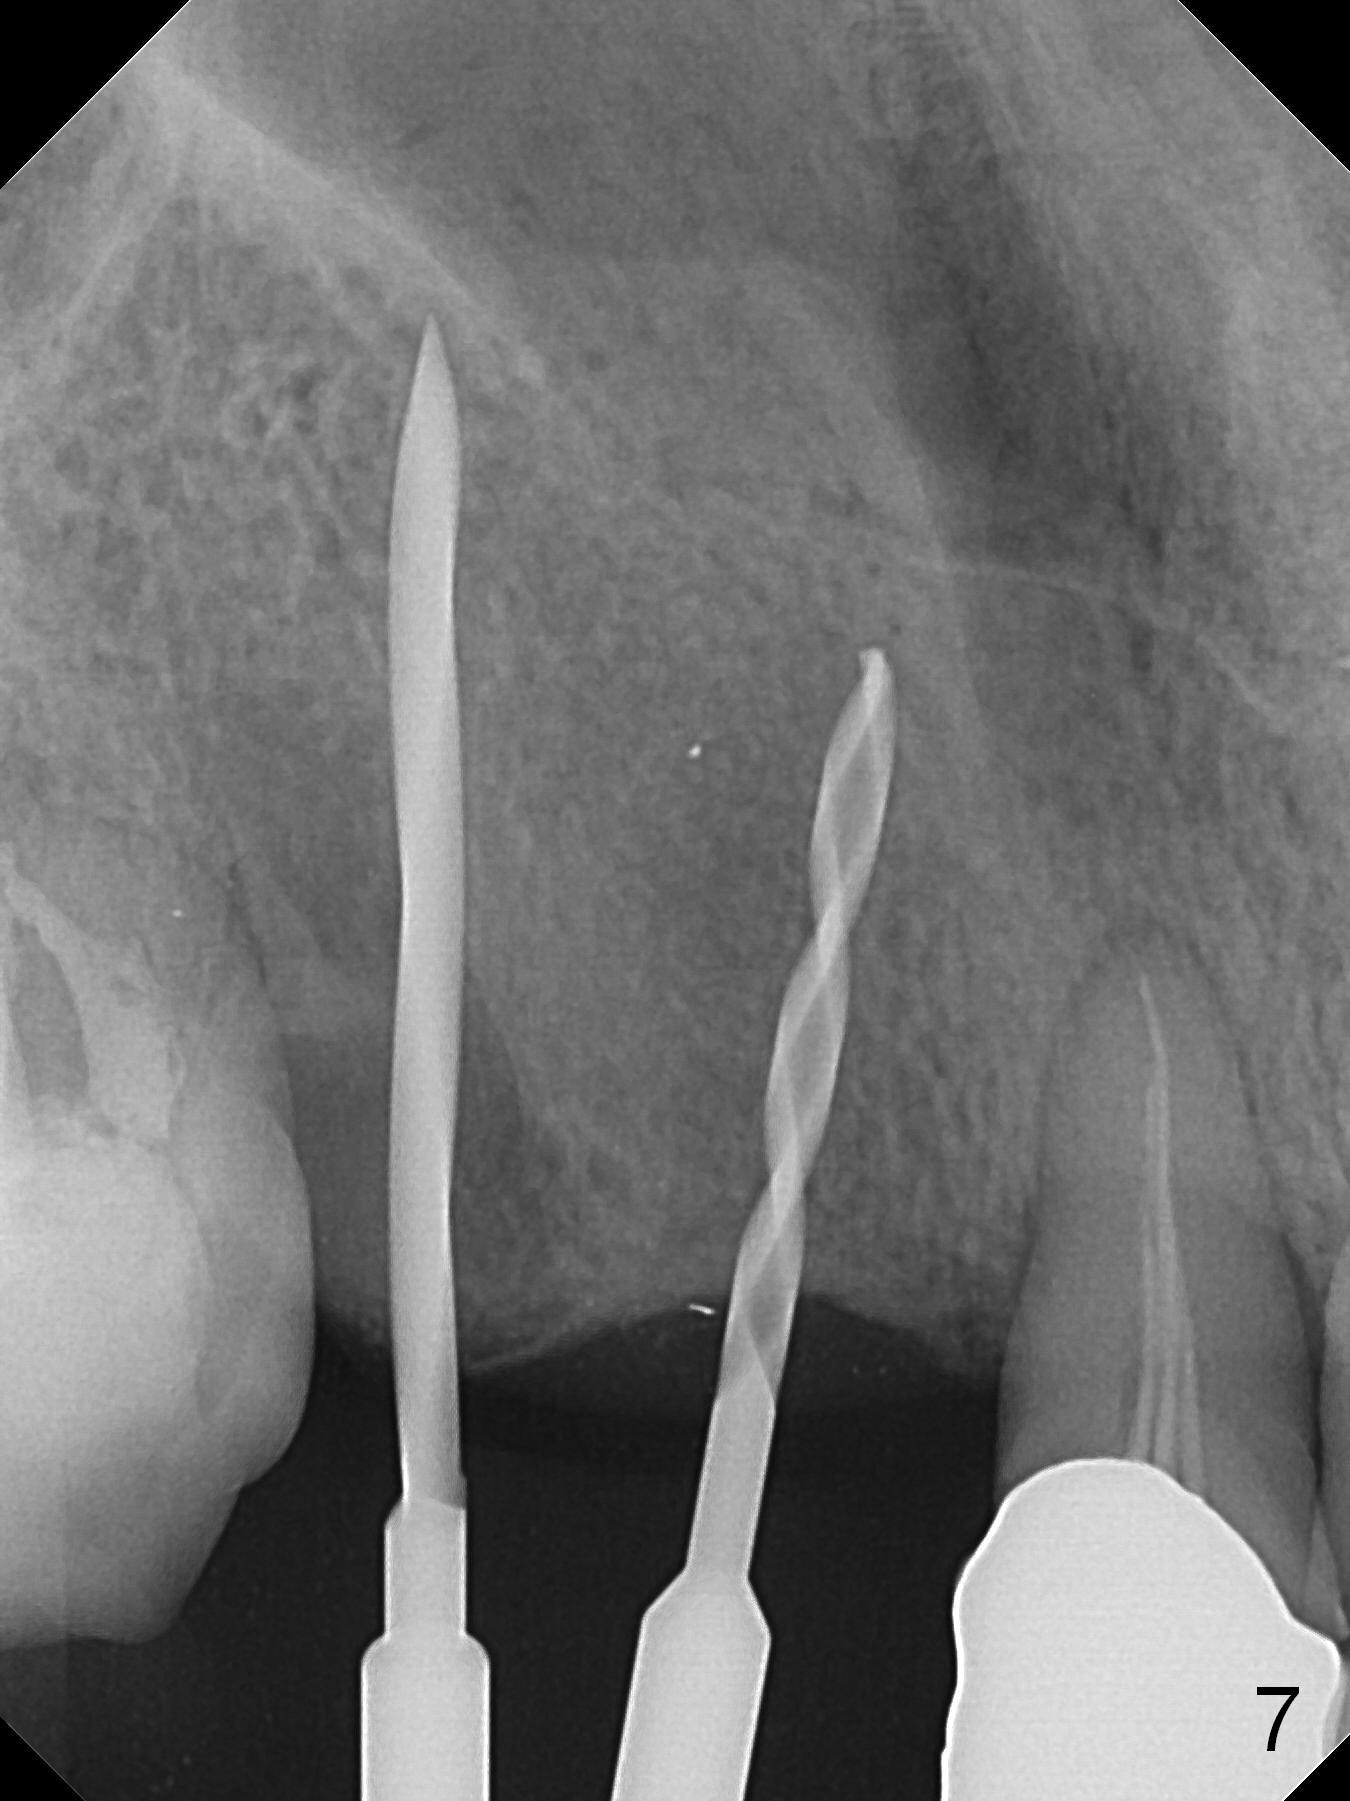

When the bridge is sectioned between #7 and 8, the tooth #6 is found non-salvageable (Fig.1). Incision shows the atrophic buccal plate at #7 (Fig.2 arrowheads); to prevent the same feature from happening at #6 with thin buccal plate, the most buccal portion of the root is preserved (socket shield (Fig.2-4: *)). The initial osteotomy is established in the palatal slope at #6 (Fig.5 circle) with 1.5 mm drill (Fig.6,7). A portion of the root is visible in Fig.6 (arrowheads). After sequential osteotomy with 2 mm, 3 mm (Fig.8) and 3.2 mm drills, a 4x15 mm implant is placed (Fig.10). To accommodate the cross bite, the coronal portion of the implant (Fig.9 white circle) is positioned close to the socket shield. It appears that the shield prevents the implant from encroaching the buccal plate.

Since the ridge at #7 is ~ 4 mm, a 2.5x14 mm 1-piece implant is placed (Fig.8) after 1.2 mm (Fig.7), and 1.5 mm drills at 12 mm and 2 mm drill at 8 mm. Later the implant is placed deeper (Fig.10). There is no bone loss 7 or 12 months postop, respectively (Fig.11,12). After Diode gingivectomy, there is papillary formation (Fig.13). No provisional is provided after impression (with the abutment torqued at #6) for oral hygiene. With access holes at #6 and 7, crowns are bonded with minimal residual cement (Fig.14 <, which is removed later). There is no hard (Fig.15,16) or soft (Fig.17 *) atrophy 26 months postop, i.e., 13 months post cementation, due to the presence of socket shield (Fig.15 <, as compared to Fig.1). In fact the tooth #8 has mobility and fremitus (short root/poor crown/root ratio, Fig.16); occlusal adjustment is done 13 months post cementation. The crown is dislodged 2 years 1 month post cementation; a prefabricated post is being tried in (Fig.18). There is no atrophy, bone loss or infection at #6 (with socket sheath (*)) or 7 two years 5 months post cementation (Fig.20-27).